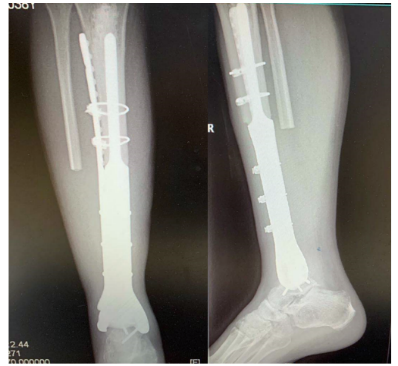

术后复查照片

1月20日,在麻醉科的协助之下,与祁伟仲博士,骨科赖少勇医生一起经历了两个半小时的努力后,林荔军主任和他的团队成功地将肿瘤切除,并为江某换上了这条3D打印个性化定制的“新腿”。现患者恢复顺利,已可在拄拐辅助下行走。

3D打印是指利用病人的影像学数据在计算机上进行三维重建,之后根据重建出来的骨头来个性化地设计假体,利用3D打印设计出来的假体相比于批量生产的假体具有匹配性好的优点,并且假体上打印出的微孔结构能帮助骨细胞长到假体内部,假体和人体的融合程度更高。